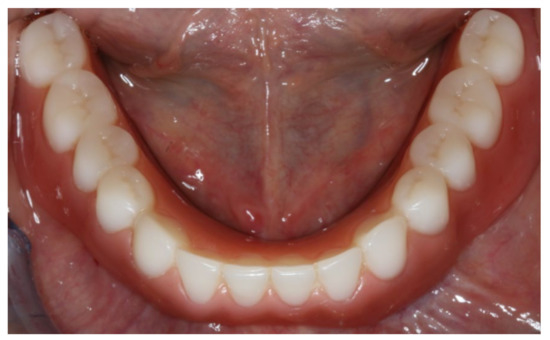

During the final appointment, the Locator abutments were tightened with torque (0.35 Nm) and the dentures were inserted. The attachment patrices were equipped with inserts producing intermediate retention (green). Occlusion, extension, retention, and aesthetics were carefully controlled and adjusted where appropriate (Figure 19, Figure 20 and Figure 21). Both dentures featured excellent retention and fit. Finally, the patient was instructed regarding insertion, removal, and maintenance of the dentures. After one week, the patient was satisfied with the new prostheses and no complications were reported or identified.

Figure 19.

Inserted implant-supported overdenture in the lower jaw.